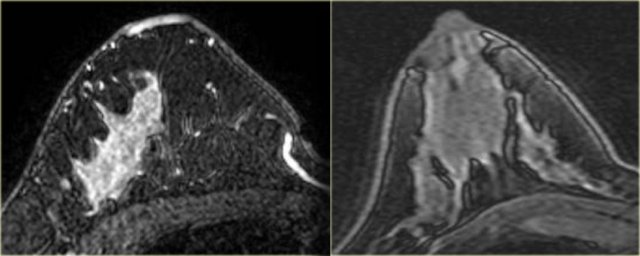

Others

Terminal duct carcinoma

On the left a large, irregular, enhancing mass in a male patient.

This was a terminal duct carcinoma.

Sarcoma with osseous differentiation

The case on the left is a patient with a sarcoma with osseous differentiation, showing less enhancement.

Adenoid cystic carcinoma

On the left an image of an irregular enhancing mass which was an adenoid cystic carcinoma.

Metaplastic carcinoma

On the left an example of a metaplastic carcinoma with rim-enhancement.

This is not necessarily a typical presentation.

There is a small area of stromal fibrosis laterally in the left breast.